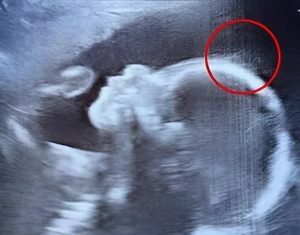

Doctors couldn’t believe what they saw during the ultrasound

When Emily Foster from Kent, England, went in for a routine ultrasound at 20 weeks pregnant, she expected to see the usual—tiny kicks, a...